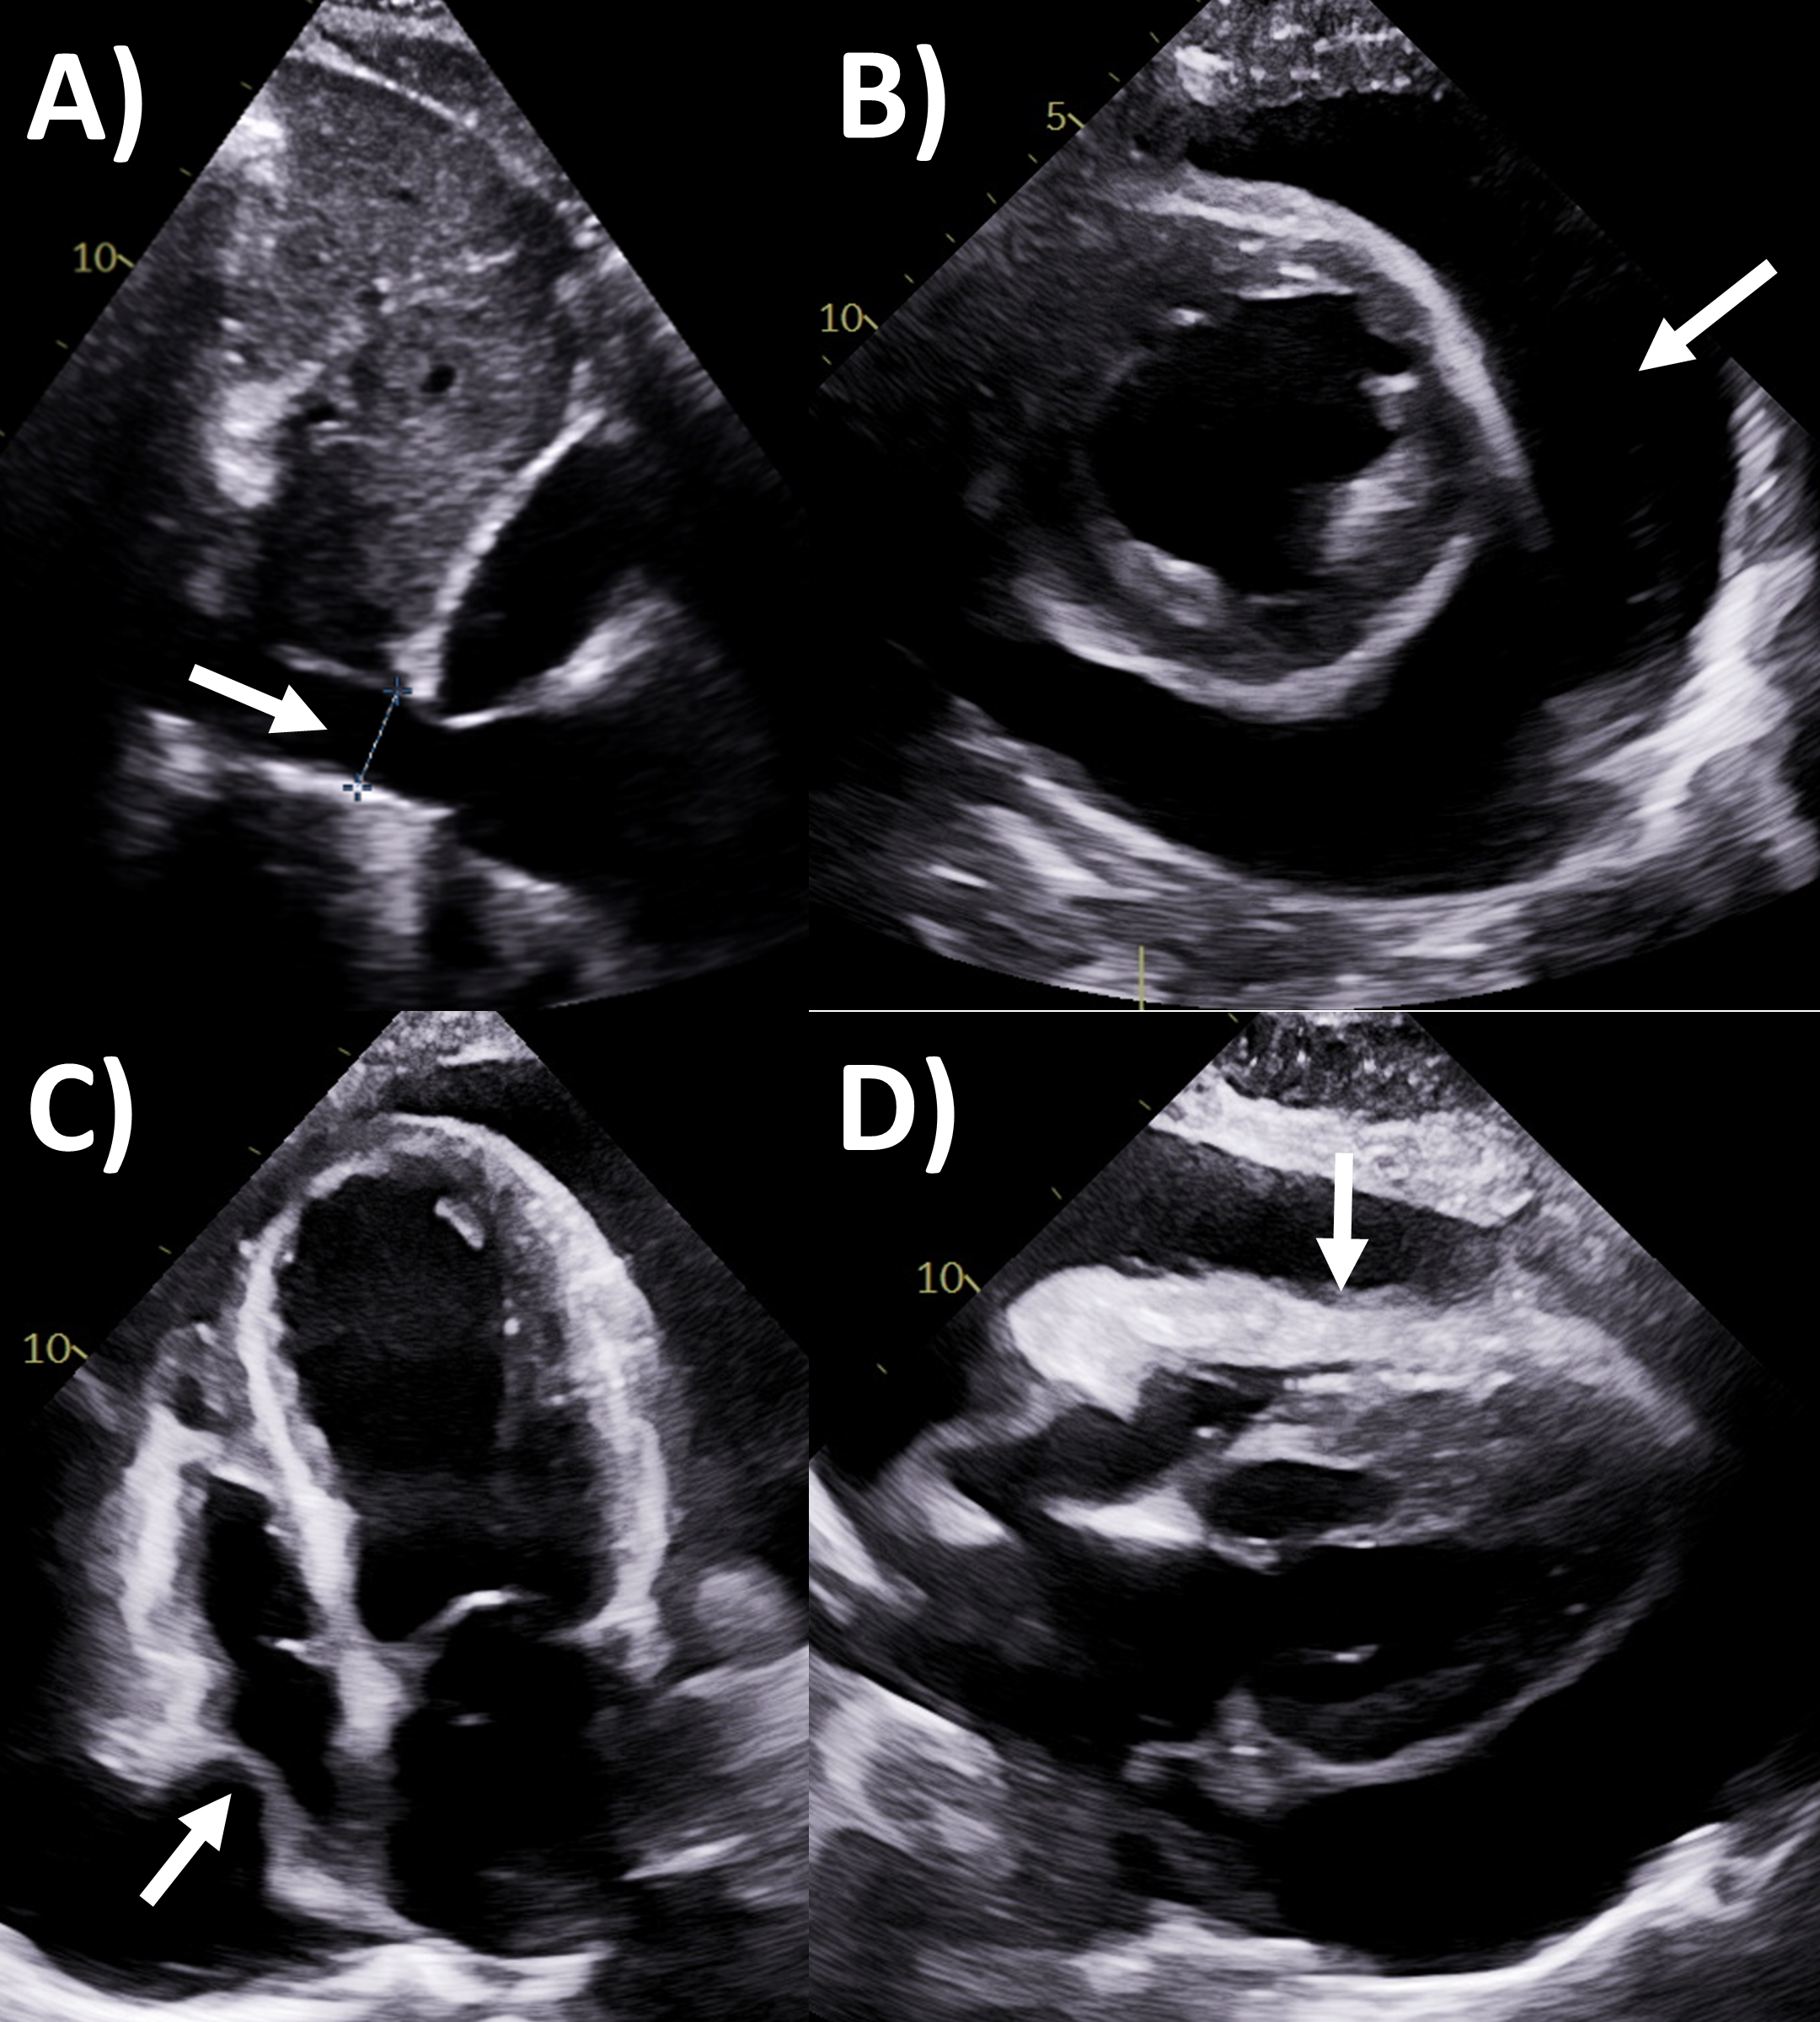

restriction or diastolic dysfunction, with several key findings shown in (Fig. 3)

Fig. 3.Multi-modality imaging evaluation of constrictive pericarditis.

Echocardiography (A) dilated inferior vena cava (2.3 cm) with minimal

Of note, in the Mayo Clinic Criteria derivation study, the presence of

respirophasic ventricular septal shift and either medial e’ velocity

Cardiac CT may assist with diagnosis of pericardial constriction if inconclusive by echocardiography alone [2]. Supportive findings include abnormal thickening 4 mm or more, pericardial calcifications (where CT is the best modality to assess this, although only 25–50% of constriction patients with calcifications), dilated inferior vena cava and atria, conical deformity of the ventricle(s), and extracardiac findings such as pleural effusion, ascites and hepatosplenomegaly [2, 45, 46, 47]. Pericardial calcification often has an irregular distribution, such as preferentially affecting the basal anterolateral left ventricle, right ventricular outflow tract, and adjacent to the mitral and tricuspid annulus [48]. If cine images of the cardiac chambers over one cardiac cycle are performed using retrospective ECG-gating, then respirophasic septal shift and wall tethering may be observed [2]. Perhaps just as valuable is CT’s role in the evaluation of the thoracic anatomy or extracardiac pathologies as part of pre-operative evaluation for pericardiectomy or other cardiothoracic surgeries, such as location of pericardial and aortic calcifications, and cardiovascular structures relative to the sternum which are especially important in redo cardiac surgery [49].

MRI is actually a valuable second-line but under-utilized imaging tool for

evaluating constrictive pericarditis [2]. Standard cine imaging with steady state

free precession or gradient echo sequences not only assess chamber size and

function, but also typical constriction findings such as abnormal

interventricular septal motion, wall tethering, conical ventricular deformities,

and dilated inferior vena cava, while free breathing sequences allows assessment

for respirophasic septal shift (Fig. 3) [2, 50]. Pericardial thickness often

increased in constrictive pericarditis can be assessed by these bright-blood

sequences or black-blood spin echo sequences, as well as dilated inferior vena

cava. Quantitative measures include lower short-axis cardiac area at

end-inspiration/end-expiration, and higher relative atrial volume index ratio

(left versus right) to be present in constrictive pericarditis [51, 52].

Acquiring phase-contrast sequences real-time over 10 seconds with free breathing

an detect mitral and tricuspid inflow, with